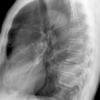

Case 3 RM & UL pneum PA

Date: 07/04/2004

Views: 5886